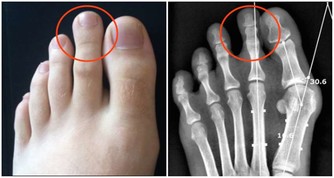

牙結石會不斷刺激牙周組織,並會壓迫牙齦影響血液迴圈,

造成牙周組織的病菌感染,引起牙齦發炎萎縮,形成牙周囊袋。

當牙周囊袋形成後,更易使食物殘渣、牙菌斑和牙結石等堆積,

這種新的堆積又更進一步的破壞更深的牙周膜,

最終會讓牙周組織全部破壞殆盡,而使牙齒難逃拔除的惡運。